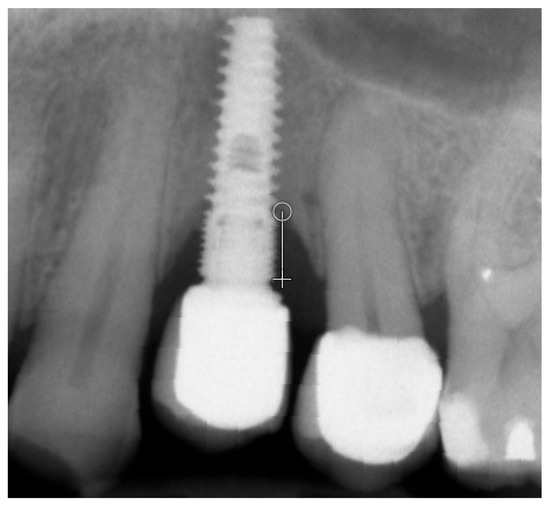

Marginal bone loss (MBL) was measured on radiological images [11] (Figure 1). The texture of X-ray images was analyzed using MaZda 4.6 freeware developed by the University of Technology in Lodz [6,12] to assess measures of corticalization in the peri-implant environment of trabecular bone (representing original bone before implant-related alterations) and soft tissue (indicative of marginal bone loss). MaZda provides both first-order (Mean Optical Density) and second-order (Differential Entropy: DifEntr; Long-Run Emphasis Moment: LngREmph) data. As the second-order data are provided for four directions in the image and the present study did not focus on directional features, the arithmetic mean of these four primary data points was used for further analysis. Regions of interest (ROIs) were marked near the neck area (Figure 2) and normalized (μ ± 3σ) to have the same mean (μ) and standard deviation (σ) of optical density within the ROI. To further reduce noise, data were limited to 6 bits. For analysis in a co-occurrence matrix, a spacing of 5 pixels was chosen. In the formulas that follow, p(i) is a normalized histogram vector (i.e., histogram entries divided by the total number of pixels in the ROI), i = 1, 2, …, and Ng denotes the number of optical density levels. The Mean Optical Density feature (a first-order feature) was calculated as follows:

Figure 1. Measurement of marginal bone loss on the radiographic images 5 years after functional loading with a single crown. The white line indicates the implant platform and the circle at the bottom of the bone loss cavity [8].